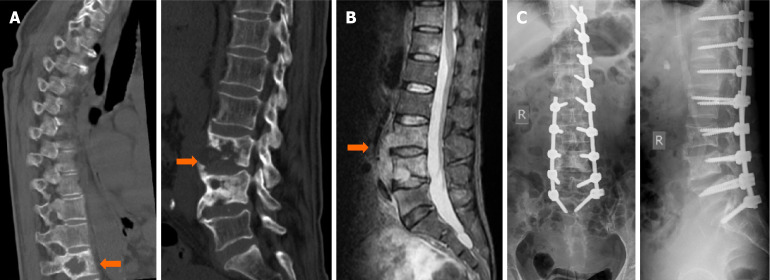

Methods: Clinical data from 24 patients with lumbar tuberculosis who underwent posterior pedicle screw fixation combined with minimally invasive anterior lesion clearance were analyzed. The Cobb angle, visual analog scale (VAS) score, and Frankel classification were statistically assessed preoperatively and postoperatively. Complications and bone graft fusion were also recorded.

Results: Wounds healed in the first stage in 22 patients; one patient developed a posterior incisional sinus tract, and one experienced postoperative tuberculosis recurrence. At the final follow-up, according to the Frankel classification, there were 1, 2, and 21 cases classified as grade C, grade D, and grade E, respectively. By the last follow-up, the Cobb angle, VAS score, and erythrocyte sedimentation rate had all decreased. Both X-ray and computed tomography images confirmed bone healing. The fusion time ranged from 3 to 9 months, with an average of 5.2 months.